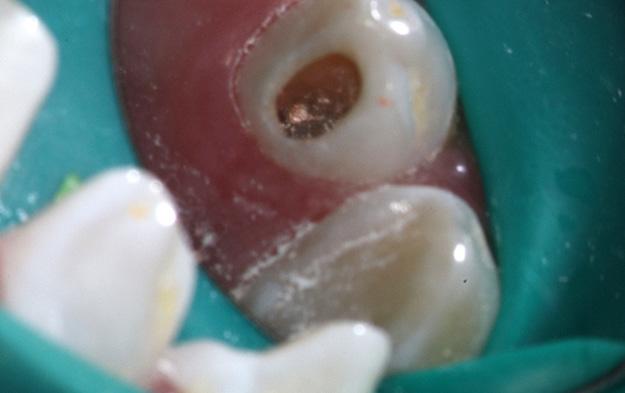

Dens Invaginatus (DI), a relatively uncommon developmental dental anomaly characterized by the invagination of enamel and dentin into the tooth structure, particularly the Type III variant which extends beyond the cementoenamel junction and possesses its own independent apical foramen, presents intricate endodontic challenges stemming from its often highly complex and unpredictable internal anatomy. Successful management requires a meticulous and tailored approach. This case report details the successful non-surgical root canal treatment of a Type III DI in a 15-year-old male's maxillary lateral incisor (tooth 12) with a pulpless, infected root canal system and a chronic apical abscess attributed to the DI defect. Preoperative evaluation involved clinical examination and periapical radiographs. While cone-beam computed tomography (CBCT) offers detailed visualization of such anomalies, its use was avoided to minimize radiation in this young patient. Clinical findings and conventional radiographs were deemed sufficient for treatment planning.

The endodontic therapy was conducted over four appointments. Access cavities were precisely prepared for both the main canal and the invagination, guided by a dental operating microscope. Working lengths were determined electronically and confirmed radiographically. The main canal was shaped using rotary files. The narrow, irregular invagination was meticulously instrumented with hand files, utilizing both EDTAC and copious sodium hypochlorite irrigation for thorough cleaning and disinfection. Calcium hydroxide mixed with Ledermix was used as the initial intracanal medicament to address infection and inflammation.

The fourth appointment involved re-access, final EDTA irrigation, and obturation. The main canal was obturated with a single gutta-percha cone and AH-26 Cement. Due to the invagination's complex morphology, a thermoplasticized injectable gutta-percha system ensured complete three-dimensional filling of this aberrant space. The access cavity was then permanently restored with composite resin to prevent microleakage.

A six-month clinical and radiographic follow-up demonstrated a successful outcome. The patient was asymptomatic with no tenderness, and the previously present sinus tract had resolved. Radiographic evaluation revealed a significant reduction in the periapical radiolucency, indicating healing of the chronic apical abscess.

In conclusion, this case underscores the critical role of meticulous chemomechanical preparation of both the main and invaginated canal systems, the strategic use of appropriate intracanal medicaments, and the application of tailored obturation techniques, such as thermoplasticized gutta-percha for complex anatomies, in achieving successful endodontic outcomes in challenging DI cases. While CBCT is a valuable diagnostic tool, this case highlights that thorough clinical assessment combined with carefully interpreted conventional radiographs can be sufficient for diagnosis and treatment planning in younger patients. Ultimately, a strong foundation in basic endodontic principles and the ability to adapt treatment strategies to the unique anatomical complexities of Dens Invaginatus remain paramount for successful management.

X-ray 1: A large periapical radiolucency in association with tooth #12, with a gutta-percha point tracing through the visible sinus tract originating from this area.

X-Ray 5: The six-month follow-up radiograph demonstrates a significant decrease in the dimensions of the radiolucent area, consistent with a favourable outcome of the endodontic treatment.